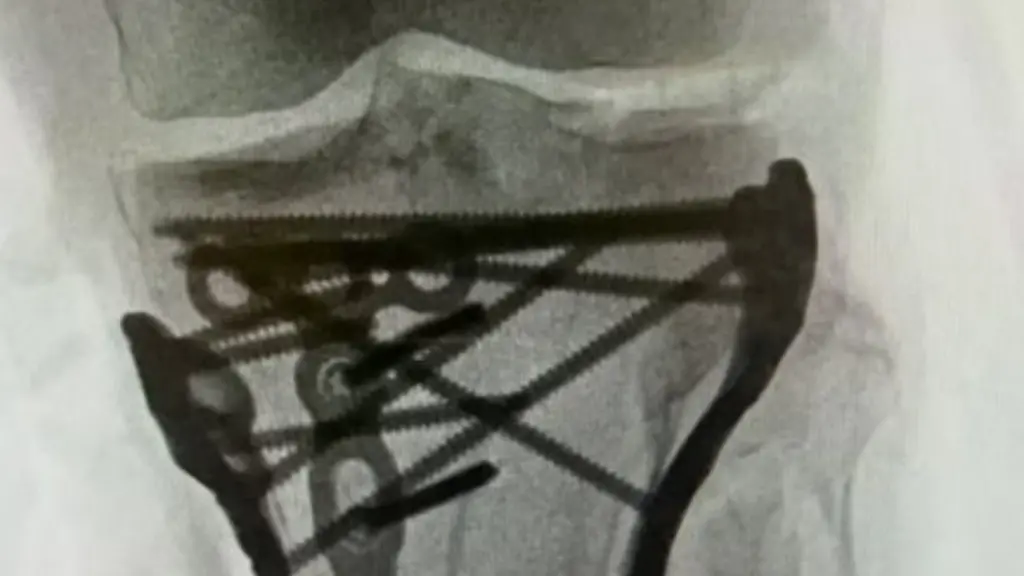

Das belegt Vonn mit Röntgenbildern, die zahlreiche Schrauben in ihrem Bein zeigen. Wegen der Schwere des Eingriffs müsse sie noch ein wenig in der Klinik bleiben, berichtete Vonn, es gehe in "Babyschritten" vorwärts. Was genau bei dem Eingriff passiert sei und was das bedeute, wolle sie "bald" erklären.